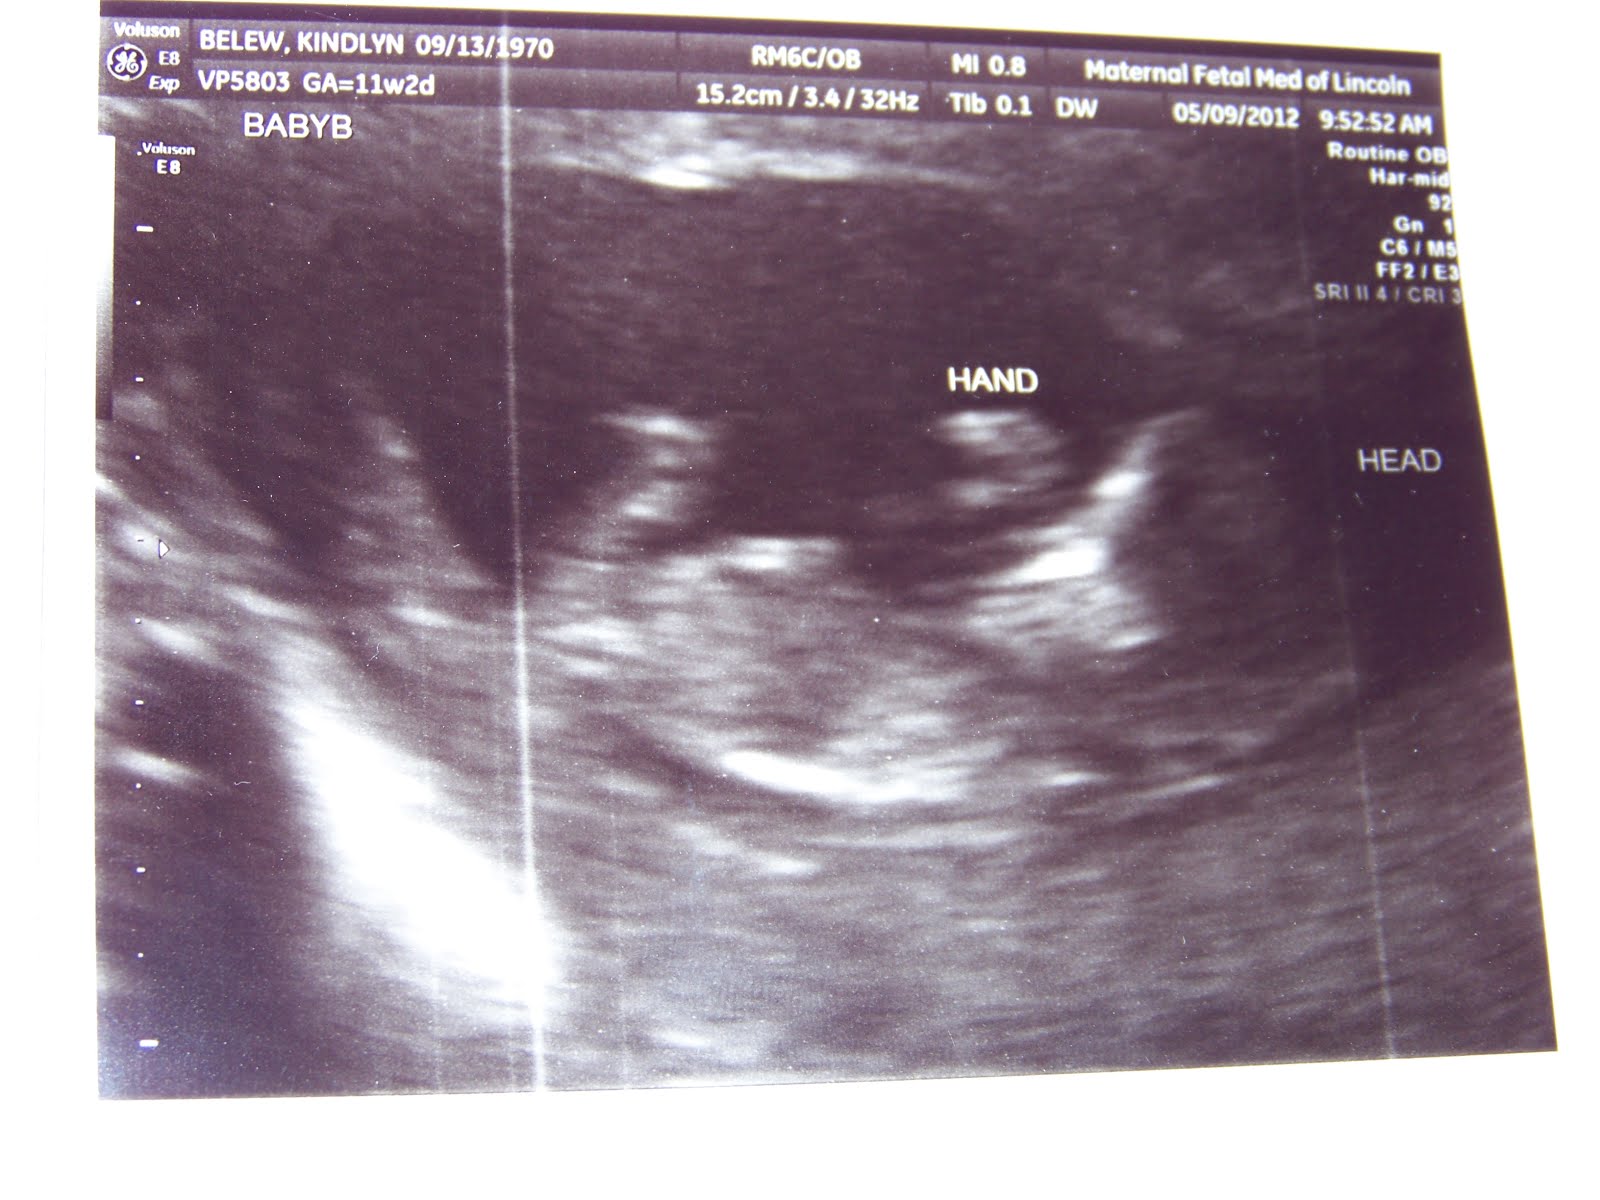

I admitted to my nurse about being a bit fearful and struggling with that. We both agreed that fear was a very common emotion in a pregnancy after a loss, especially after a devastating loss like we suffered when Calleigh Joy went to heaven instead of living with us. So we went in the room, I laid on the table and the cold gel got squirted on my tummy. Burrrrrrr, I hadn’t had an ultrasound like that since Calleigh. But I didn’t allow my mind to go there. I searched the screen for a fluttering heart, but what I saw first put all my worries at ease. Two very squirmy little babies. That would explain not finding their heartbeats last night! The nurse was having a hard time “capturing” it on the screen to hear them. They kept moving out of the frame! She did manage to get some pictures, probably not as clear as she would’ve liked but they were so fun to watch.

So here they are! Our little peaches!